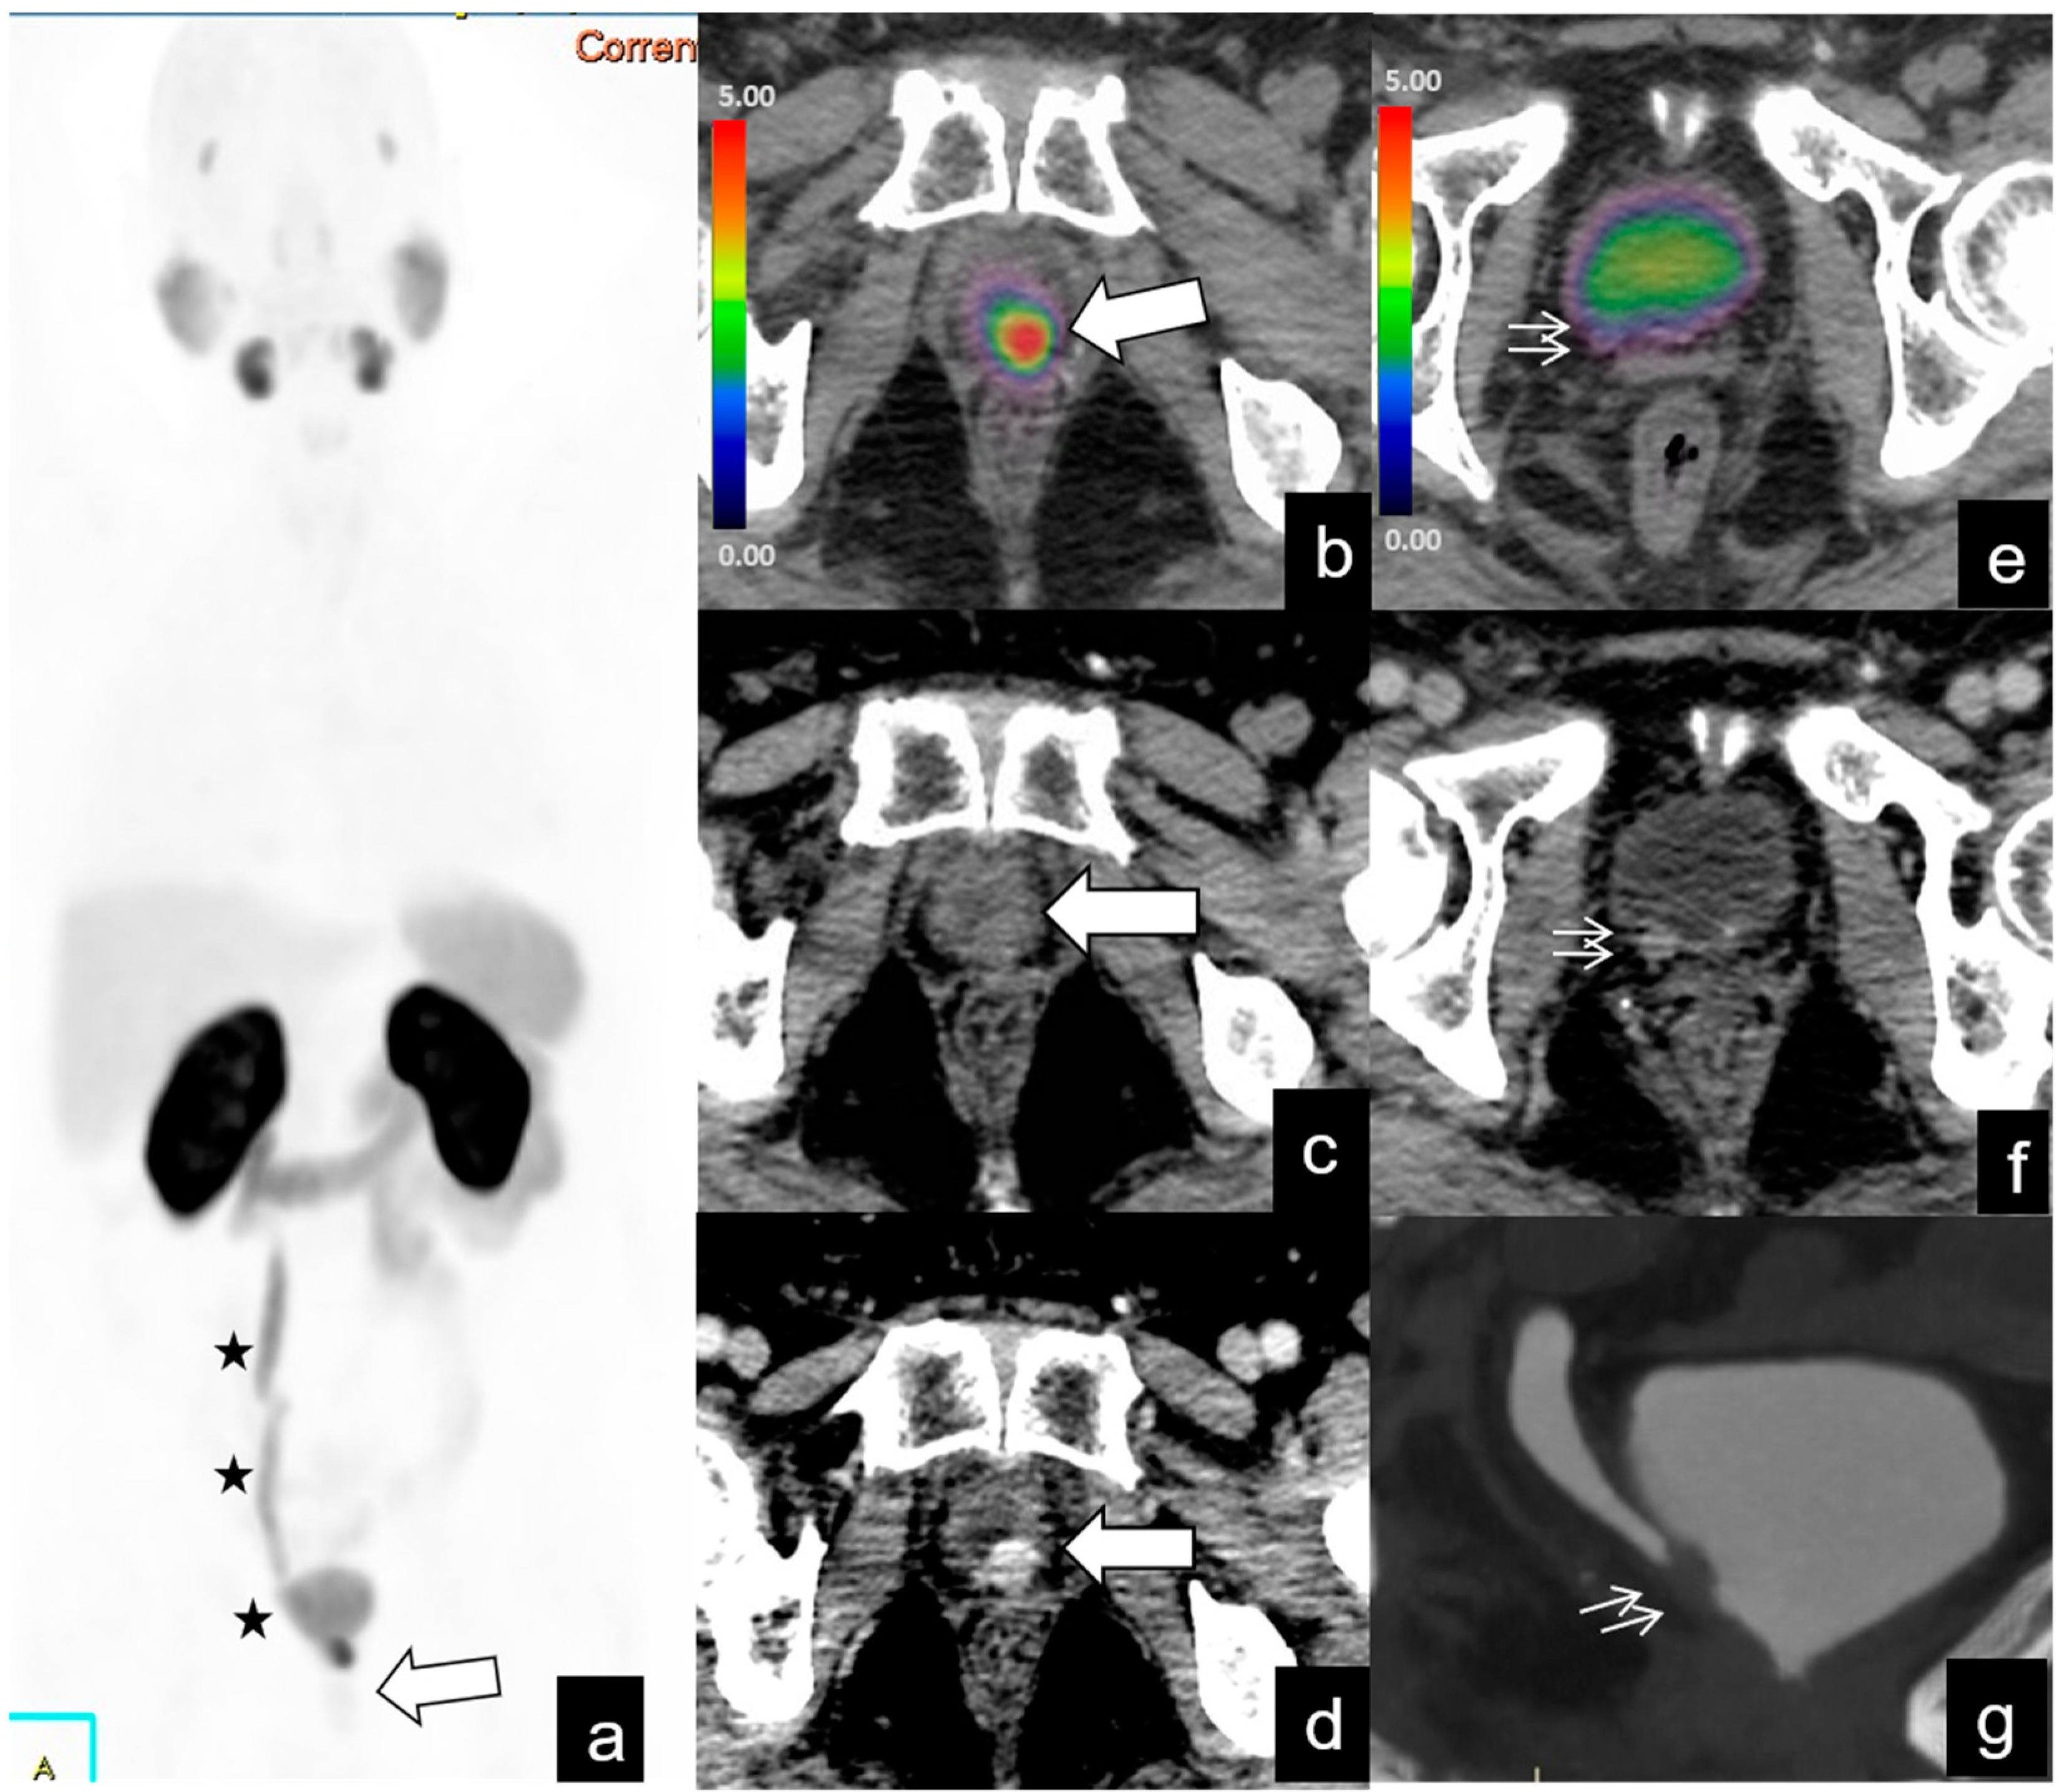

| Local recurrence | 42/128 (32%) | 12 | 2.1–46 | 9.6 | 3–53 |

| Lymph-node metastases | |||||

| Abdominopelvic | 39/128 (30%) | 24 | 1–73 | 7.3 | 2–19 |

| Bone metastases | 20/128 (15%) | 19 | 1.9–70 | ||